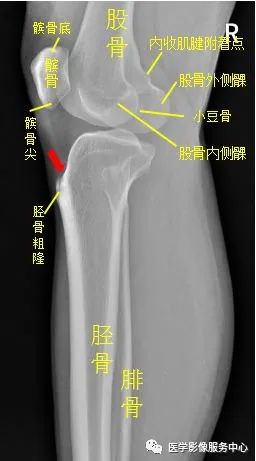

(九)膝关节

右侧胫骨粗隆可见低密度骨折线,骨折处稍分离移位,考虑为右侧胫骨粗隆骨折。